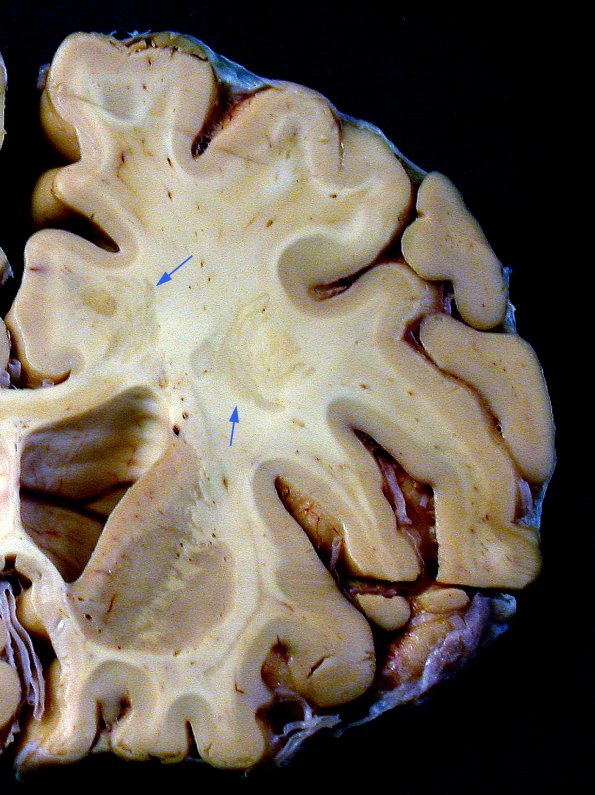

Washington University Experience | MYELIN (IMMUNE-MEDIATED) | Balo Concentric Sclerosis | 3B1 Balo Sclerosis (Claire Coire image, 2009 CANP Unknown 2) gross Hemisphere 1 copy - Copy

Coronal section shows unusual serpiginous and concentric demyelinative foci in the white matter of this hemisphere (special thanks to Claire Coire for this image)